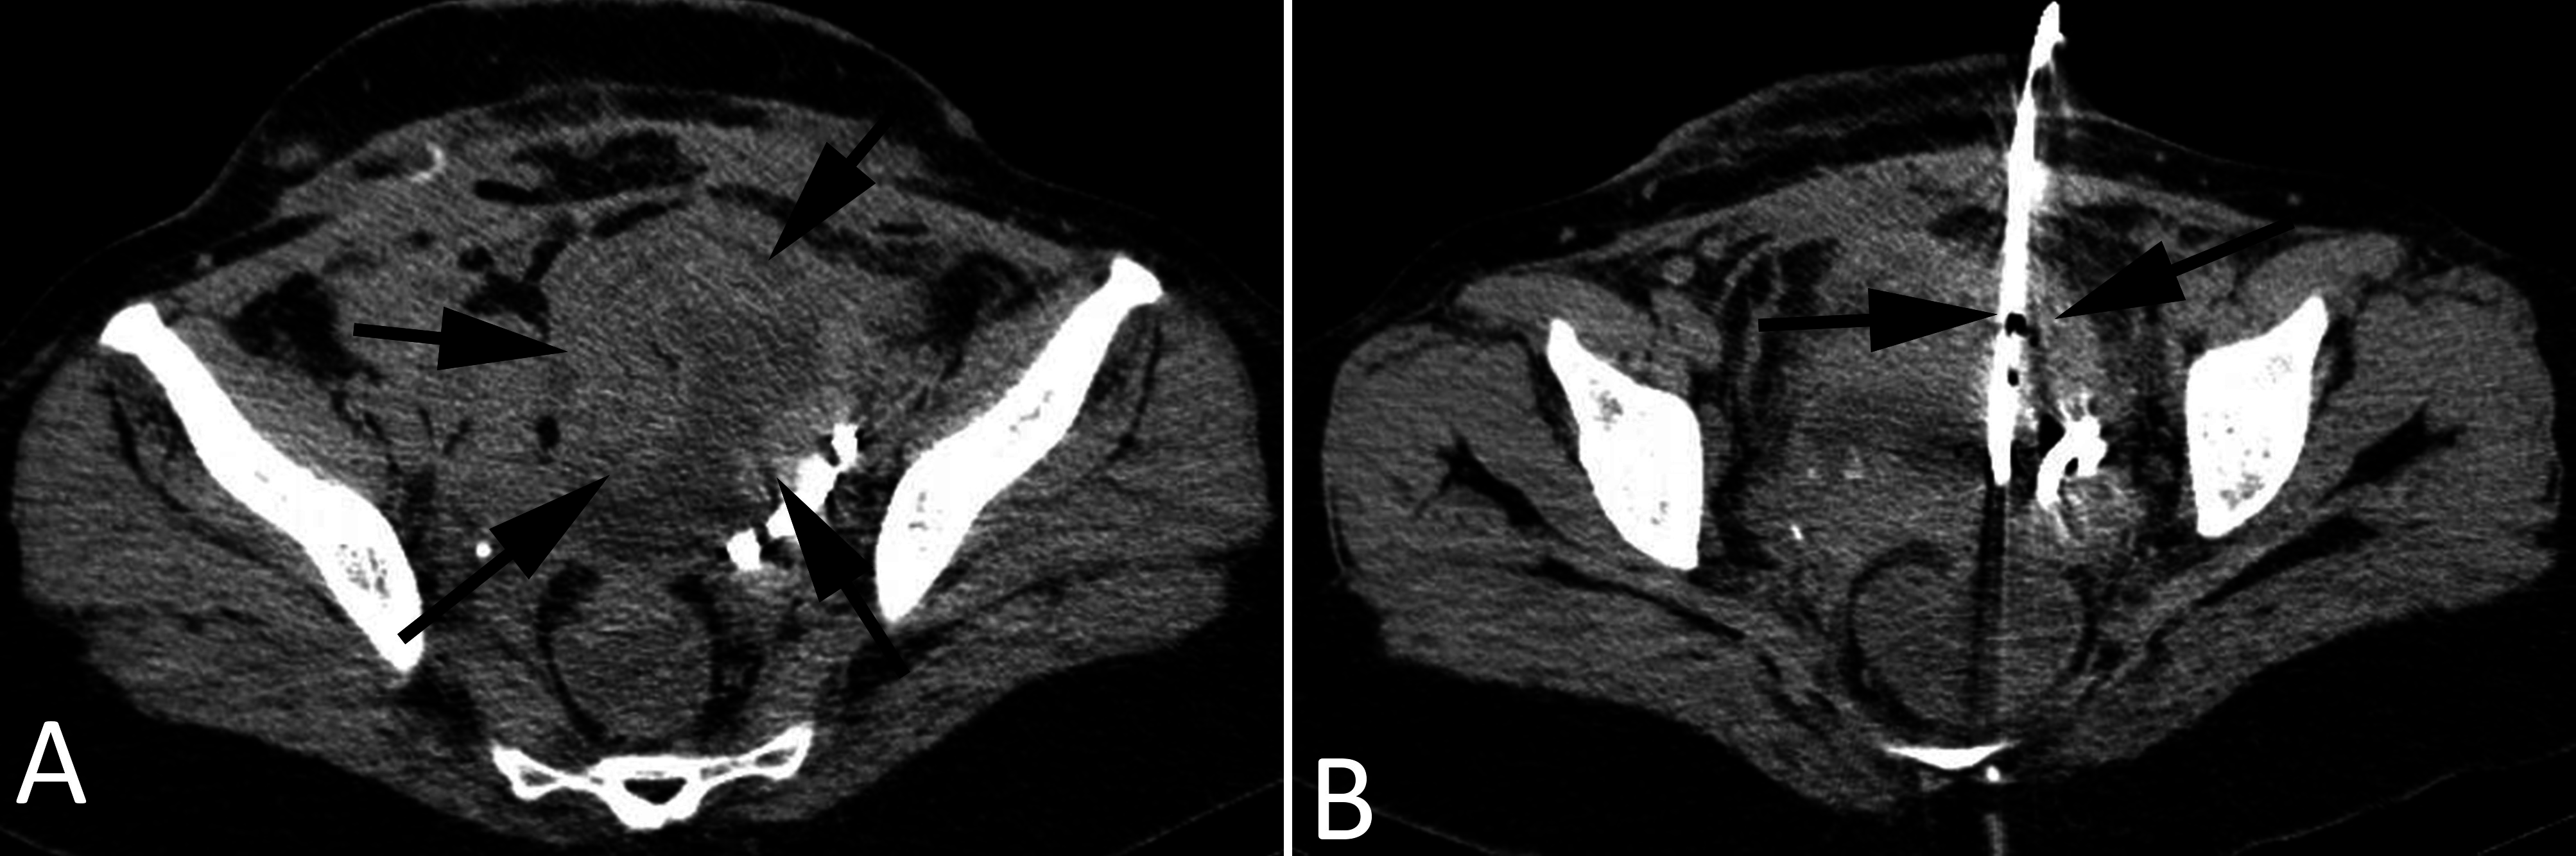

From www.research-journal.net

Computed tomographyguided percutaneous drainage of a pelvic abscess Back Abscess Surgery The aim of the procedure is to drain the abscess, remove unhealthy tissues and ensure the cavity does not close to prevent. Surgery is often the recommended treatment for spinal epidural abscess. once your doctor has located an sca, they will have to drain or remove the abscess. what does the operation involve? This means that your surgeon. Back Abscess Surgery.